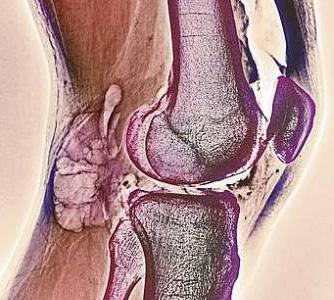

Lefevre rivela che lo studio si è concentrato su alcune cellule che svolgono un ruolo chiave nella distruzione dei tessuti innescata dalla malattia: i fibroblasti che si trovano nella sinovia, la sottile membrana che riveste le articolazioni. La loro capacità di penetrare nei vasi sanguigni abbandonando la loro sede iniziale era già stata verificata in vitro, ma secondo la giovane ricercatrice «nessuno aveva mai dimostrato che anche nell’organismo potessero viaggiare nel circolo sanguigno». «Per mettere alla prova la teoria – afferma Lefevre - abbiamo iniettato da un lato dell’animale frammenti di cartilagine proveniente da articolazioni umane sane, insieme però con fibroblasti prelevati da pazienti con artrite reumatoide. Dall’altra parte dell’animale da laboratorio è stato invece iniettato solo tessuto cartilagineo sano».

Passati 60 giorni i sistemi di analisi hanno rivelato che le cellule provenienti dalle articolazioni malate erano entrate nel circolo sanguigno arrivando nell’area in cui era stato inserito il tessuto sano. La cosa più straordinaria è stata notare che questi fibroblasti avevano già cominciato a danneggiare la cartilagine appena impiantata. La ricercatrice, già premiata al congresso della Società tedesca di medicina interna per i suoi studi quando era ancora studentessa, precisa però che la migrazione delle cellule è solo uno dei fattori in gioco nello sviluppo della malattia. Per contrastare dolore e disabilità è dunque essenziale proseguire gli studi in questa direzione facendo tesoro di quanto fin’ora scoperto.